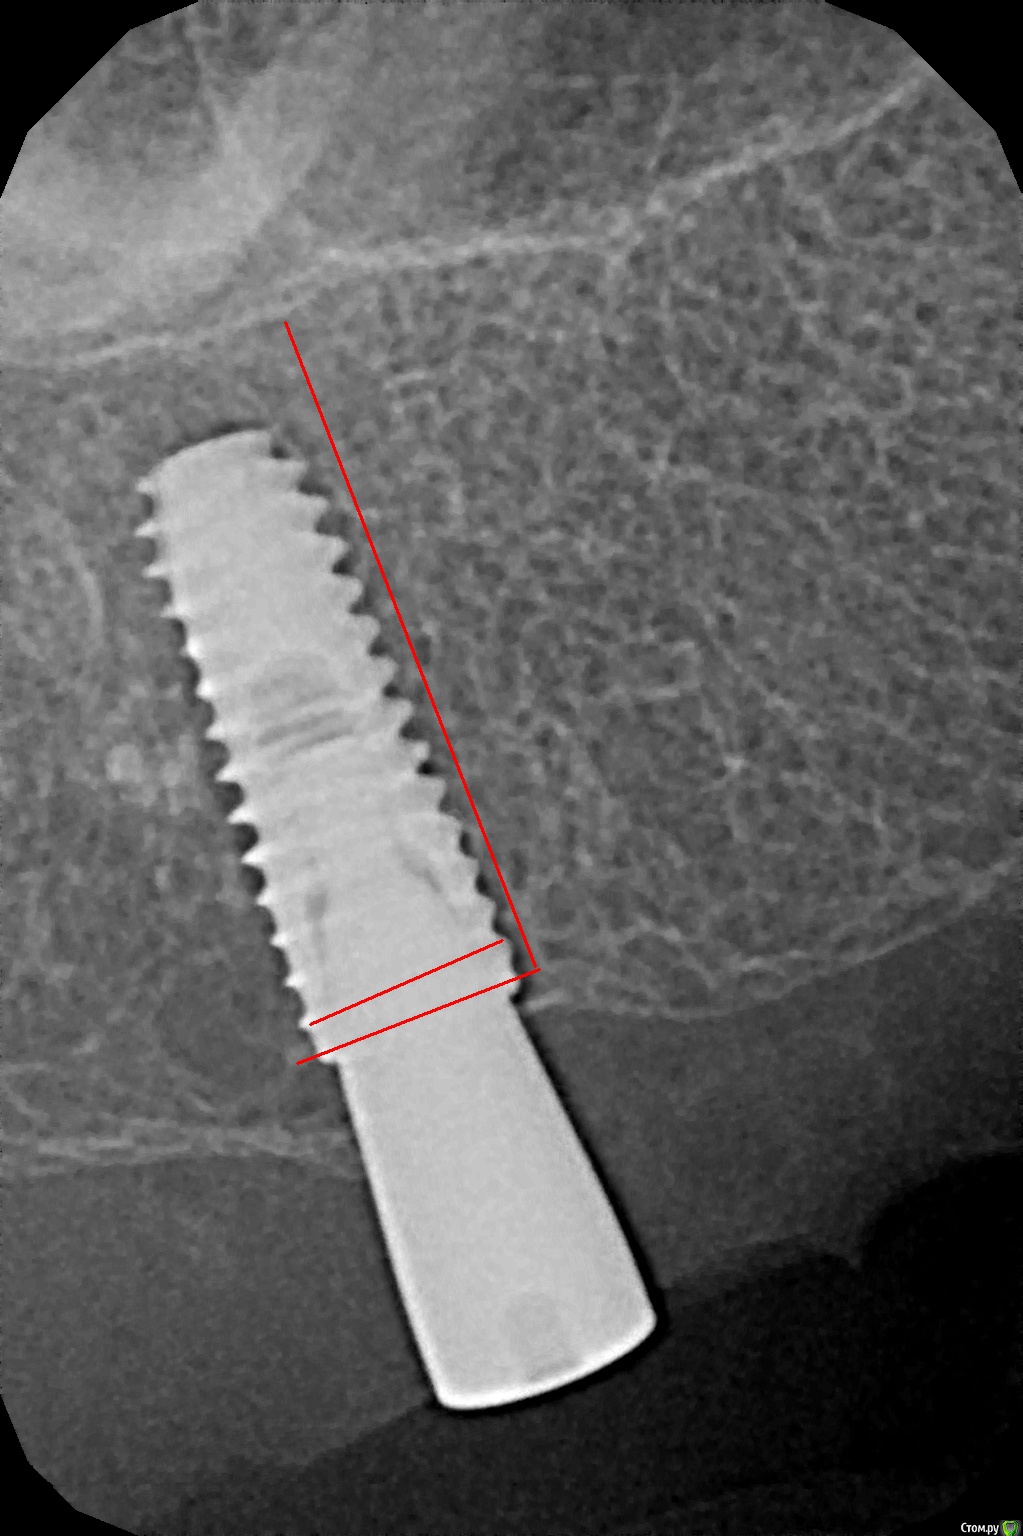

kamranchick Опубликовано 26 декабря, 2016 Автор Поделиться Опубликовано 26 декабря, 2016 По просьбе криокова.Убрал имплантат с области 17. кюретаж, ничего нет в лунке(мягких тканей итд) глубиномером все проверил, ни перфораций, ничего такого, при оказывании силы на лунку, она начинала складываться(кость)Напомню что лунку я подготовливал компресионным набором, установлен имплантат был 4.0 на 11.5ммРешил подготовить новое ложе в области 1.6.прошел пилотной фрезой 2.0 и начал сразу ставить имплантат 5.0 на 13 мм.торк - 10. или 8. решил сразу поставить формирователь. я хз блин как ложе готовить. и что надо для этого.Думаю надо было может бикортиально зафиксироваться. 1 Ссылка на комментарий

kriokov Опубликовано 26 декабря, 2016 Поделиться Опубликовано 26 декабря, 2016 торк - 10. или 8. решил сразу поставить формирователь. я хз блин как ложе готовить. и что надо для этого.Думаю надо было может бикортиально зафиксироваться. я бы фдм не решился, загушил бы. Про бикортикально-- думаю выход, чуть глубже бы пилотником и суперлайн встал бы в кортикальную дна синуса. Оно и так не плохо, при такой длине болта 1 Ссылка на комментарий

Zorrro Опубликовано 5 марта, 2017 Поделиться Опубликовано 5 марта, 2017 (изменено) Надо с формирователем походить пару месяцев.Пассивная нагрузка это то ,что нужно для тренировки кости. Ну и бикортикально конечно лучше в этом случае,если при немедленной нагрузке при 2-х миллиметрах кости апикально удаётся добиться торка за 30 на неагресивном анкилосе ,при длине импланта 17мм ,то и в вашем случаеэто добавит ,так необходимых, парочку N·m... Только обязательно надо перфорировать кортикалку,иначе имплант упрётся в неё и торк будет снова нулевой.имхо Изменено 5 марта, 2017 пользователем Zorrro Ссылка на комментарий